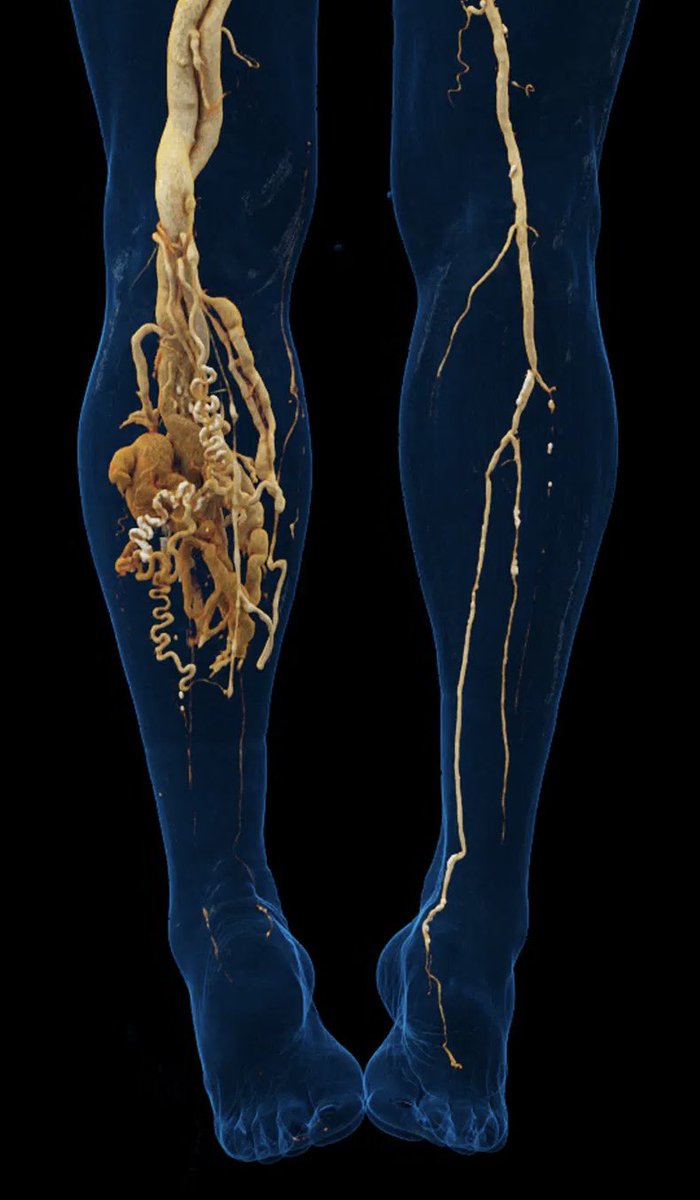

يشرفني المشاركة في المؤتمر العلمي الثالث للقدم السكرية لوزارة الصحة بجدة ممثلاً للجمعية السعودية للأشعة التداخلية متحدثاً عن الحلول العلاجية (القسطرة) بعد فشل الحلول الجراحية وبالله التوفيق @sirs_ksa

🔵 بحمد الله تم تدشين عيادة الاشعة التداخلية والقسطرة ومن اهم الخدمات المقدمه هي إعادة فتح شرايين القدم وتحسين التروية لمنع البتر والغرغرينا

صحي / "مدينة سعود الطبية" تدشّن خدمة علاج القدم السكرية والغرغرينا بالأشعة التداخلية spa.gov.sa/link/uvgp via